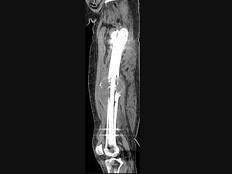

问题 男,18岁,右股骨肿瘤术后,出现大腿中段疼痛,夜间尤甚,结合CT图像,最可能的诊断是?(?)

选项 A.骨纤维肉瘤 B.尤文肉瘤 C.骨肉瘤 D.成骨性骨转移瘤 E.化脓性骨髓炎

答案 C